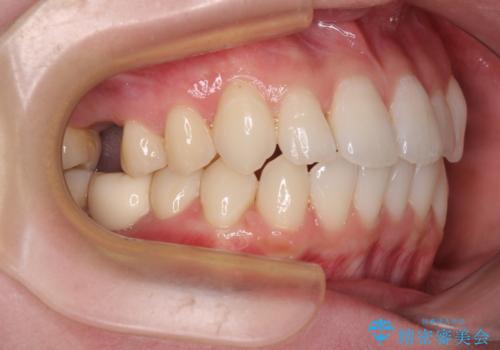

- 2、3年後にワーキングホリデーで海外に行くため、その前に歯列やむし歯をきれいにしたいとのことで来院された患者様です。

抜歯の必要な右上の奥歯は事前に抜歯をし、インビザラインにて上下歯列を整えることとしました。

矯正治療後半に奥歯の補綴治療が必要な歯にはオールセラミッククラウンを装着し、インビザラインで最終的に仕上げることとしました。